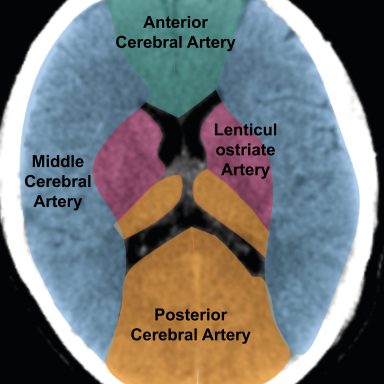

Learn moreAcute Pathology on Head CT

A head CT is the most common referral of cross-sectional imaging made by emergency departments. This package provides teaching and training using unenhanced CT images with examples of common abnormalities such as ischaemia, haemorrhage and space occupying lesions.